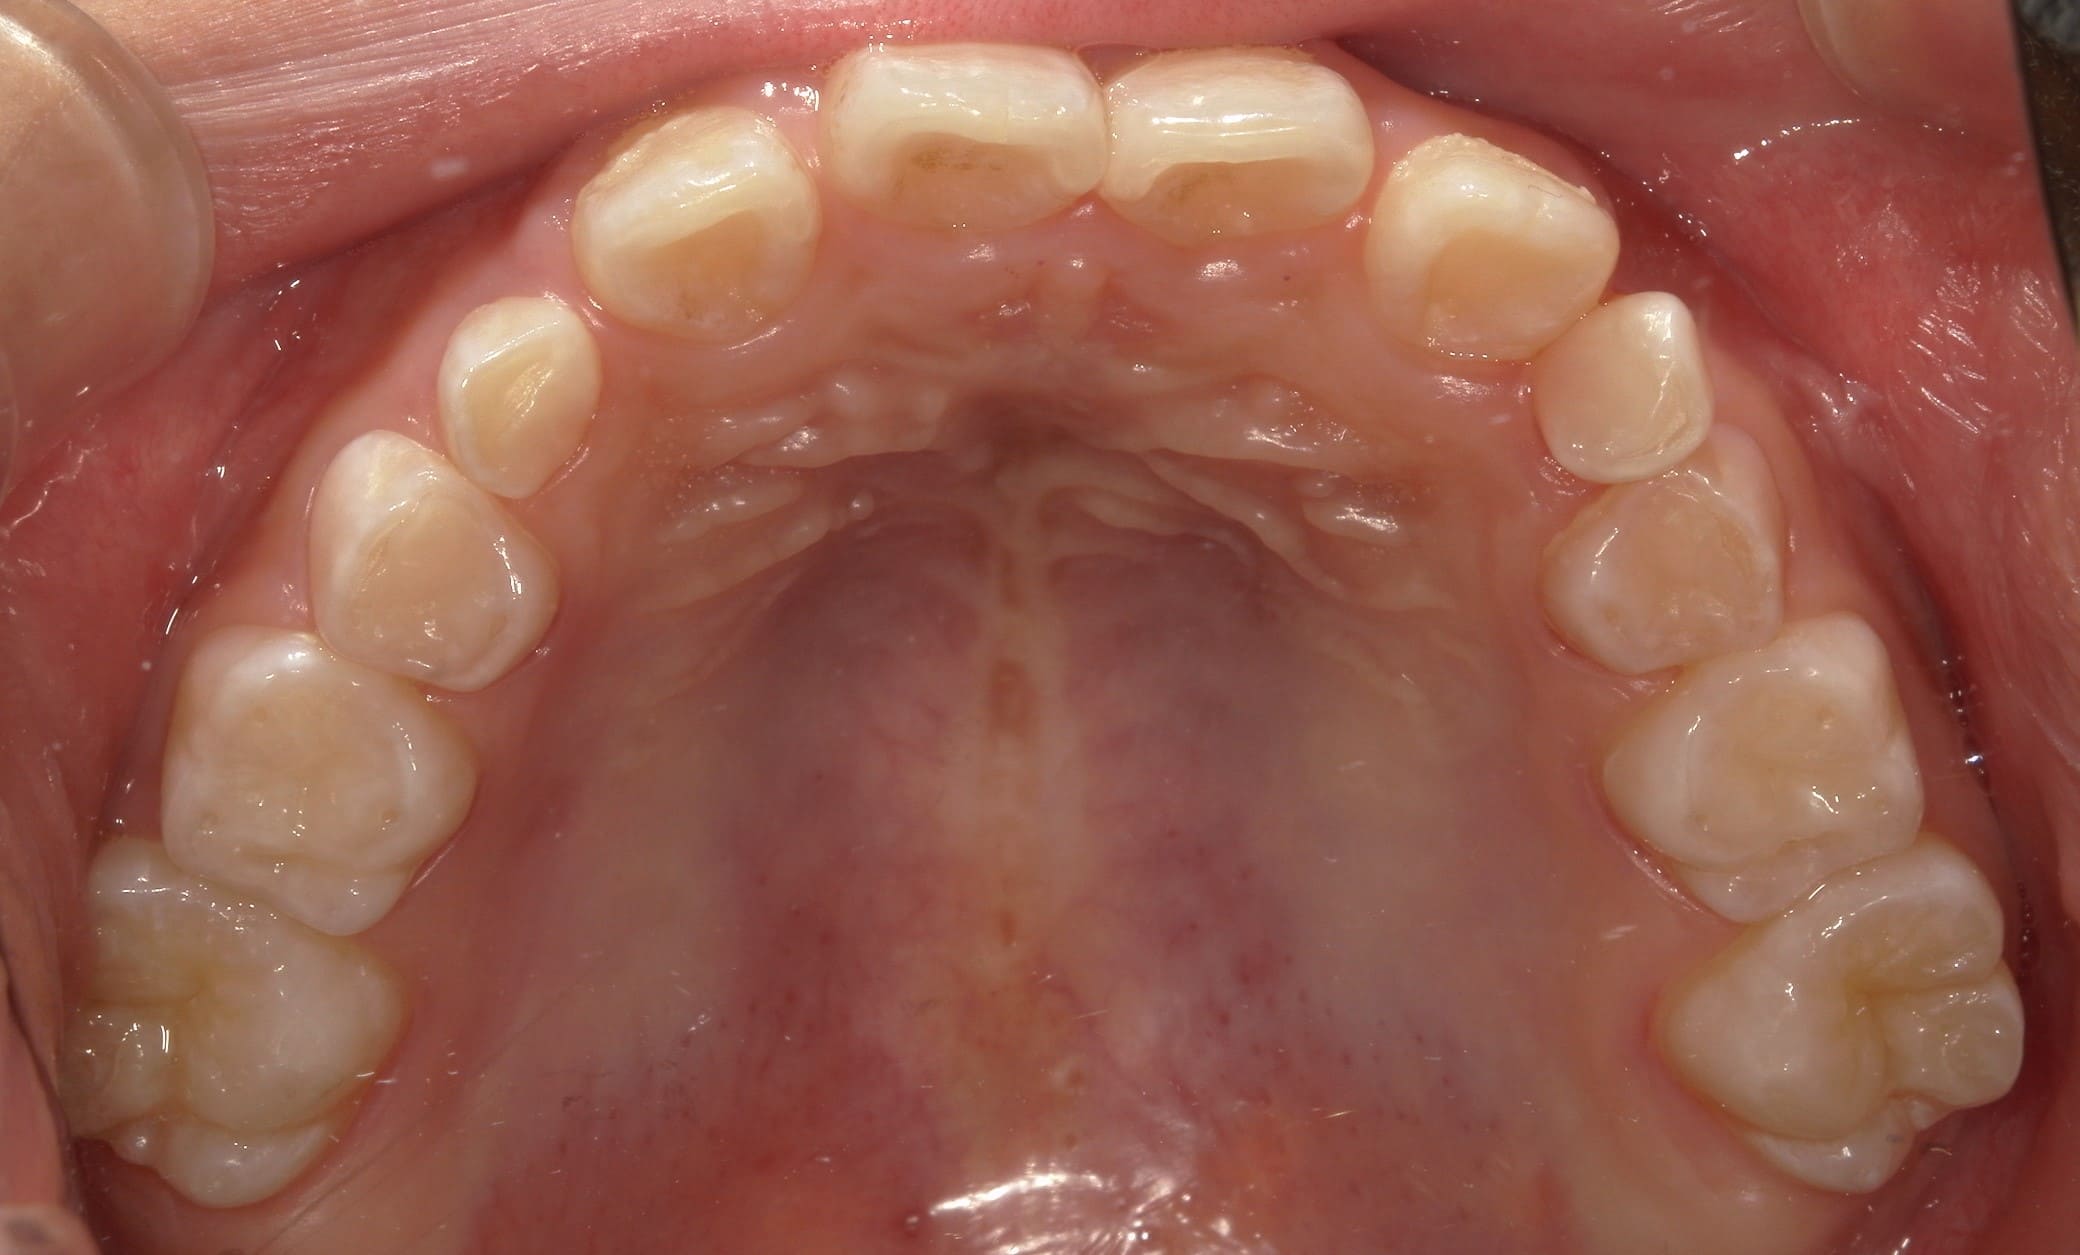

| 年齢・性別 | 8歳9ヶ月の女児 |

|---|---|

| 主訴 | 歯並びの乱れを気にされて来院された患者様です。将来的なスペース不足と歯のねじれ(翼状捻転)が懸念されました。 |

| 治療期間・回数 | 2年10ヶ月・19回 |

| 費用 | 430,000円(税別) |